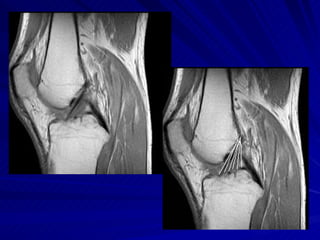

Joelho O estudo do joelho por RM é seguramente o método de imagem mais eficiente para demonstrar a anatomia e as eventuais alterações degenerativas e/ou decorrentes de traumas nesta articulação.

Joelho Posicionamento do Paciente: conforto e estabilidade; Fazer uso de bobina de RM; Series: Fat/sup – supressão de gordura e series sensíveis a presença de liquido extra e intra articular devem fazer parte desse protocolo.

Series Axial localizador: identificar a articulação DP (densidade de prótons) T2, T2* Coronal T1 FAT/SUP: supressão de gordura